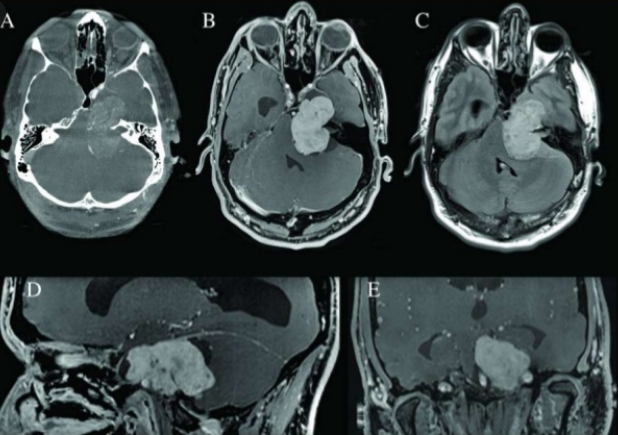

在具有遗传风险的肿瘤中,在某些情况下,神经鞘瘤是由遗传病引起的。在神经鞘瘤中,三叉神经鞘瘤是比较常见的类型,是二常见的神经鞘瘤,仅次于常见的听神经鞘瘤。三叉神经鞘瘤是一种发生于颅底、起源于雪旺细胞的颅内外周神经鞘瘤。雪旺细胞是一种胶质细胞,帮助保护周围神经系统神经元传递信息和指令。这些细胞通过在神经细胞周围形成一层叫做髓鞘的保护层来做到这一点。那么,三叉神经鞘瘤会遗传吗?

对此,James T.Rutka教授表示,大多数神经鞘瘤不是遗传性的。多数是偶然发生的,并且是单一的肿瘤。在某些情况下,由于潜在的遗传疾病如神经纤维瘤病2(NF2)、神经纤维瘤病或卡尼综合征,患者会发展成神经鞘瘤(或多发性神经鞘瘤)。这些疾病以常染色体显性遗传。这意味着在每个细胞中只有一个负责基因的拷贝发生变化(突变)就足以导致这种情况的特征。虽然神经鞘瘤可能是由遗传病引起的,但三叉神经鞘瘤本身是不会遗传的,三叉神经鞘瘤是良性的,它们生长缓慢。虽然它们不会侵入大脑,但当它们的体积增大时,会对大脑造成压力。当肿瘤变大时,也会伤害其他神经。

如何治疗三叉神经鞘瘤?

目前三叉神经鞘瘤主要治疗方法是手术切除,有几种不同的手术方法可用来切除颅底肿瘤。选择什么样的手术取决于肿瘤的类型、位置和其他因素,包括病人的整体健康状况以及肿瘤是良性还是恶性。如果三叉神经鞘瘤不能完全切除,手术后可使用放射治疗。